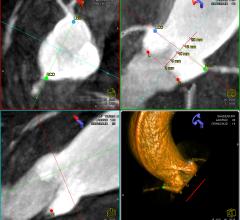

Agfa HealthCare announced that Hunt Regional Healthcare, Greenville, Texas, has upgraded its Agfa HealthCare picture archive and communication system (PACS) to Impax 6.5 and installed Agfa HealthCare's Cardiology PACS and Xero Viewer to deliver a consolidated view and centralized management of patient, image and information data. With the addition of Agfa HealthCare's Xero Viewer, physicians are able to access the nearly 100,000 imaging exams and reports done each year, on virtually any Hunt Regional facility device. Because the information is web-based, physicians can access the results in real time.